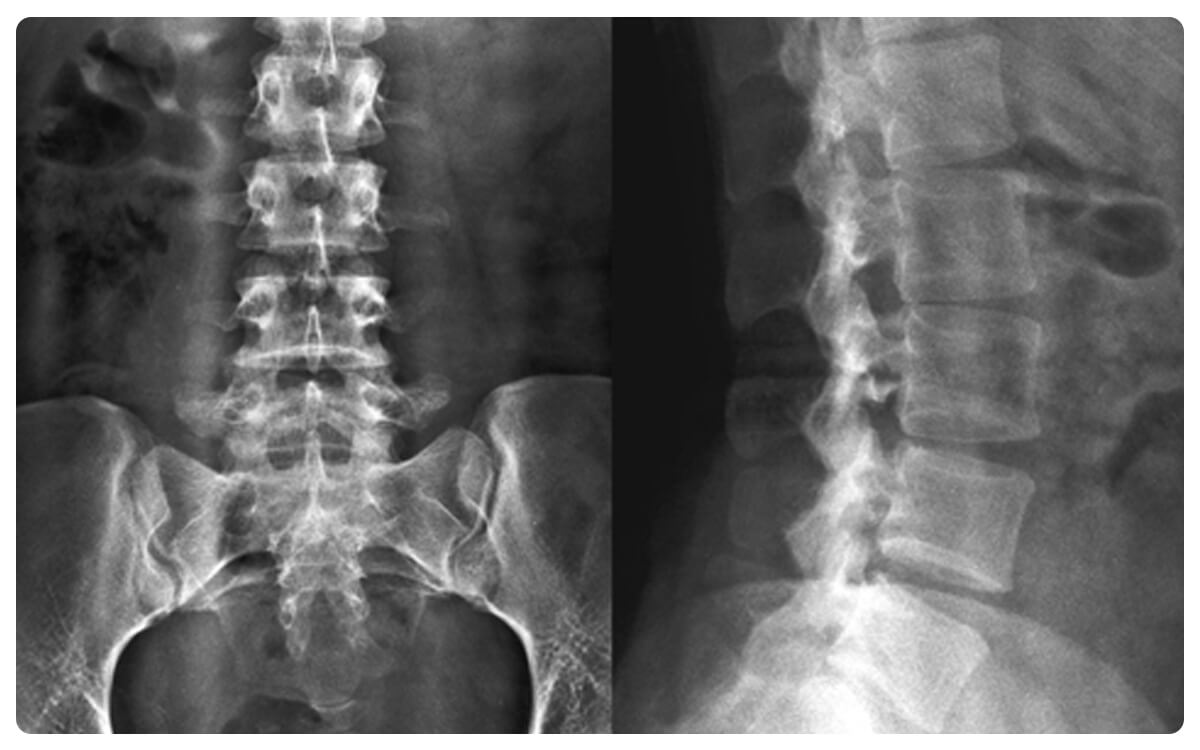

La Radiografía de Columna Lumbosacra en proyecciones Anteroposterior (AP) y Lateral se destaca como una herramienta esencial en la radiología diagnóstica, brindando una visión detallada y completa de la anatomía y posibles afecciones de la región lumbosacra. A través de la emisión controlada de radiación, estas técnicas no invasivas proporcionan imágenes bidimensionales que permiten la evaluación de las vértebras, articulaciones y tejidos circundantes en la zona lumbar y sacra desde ángulos frontales y laterales.

Las Radiografías de Columna Lumbosacra en proyecciones AP y lateral desempeñan un papel crucial en la detección y diagnóstico de hernias discales, desviaciones vertebrales, fracturas y otras patologías que afectan esta área anatómica, proporcionando información esencial para la toma de decisiones clínicas informadas y el manejo adecuado de las afecciones lumbosacras.